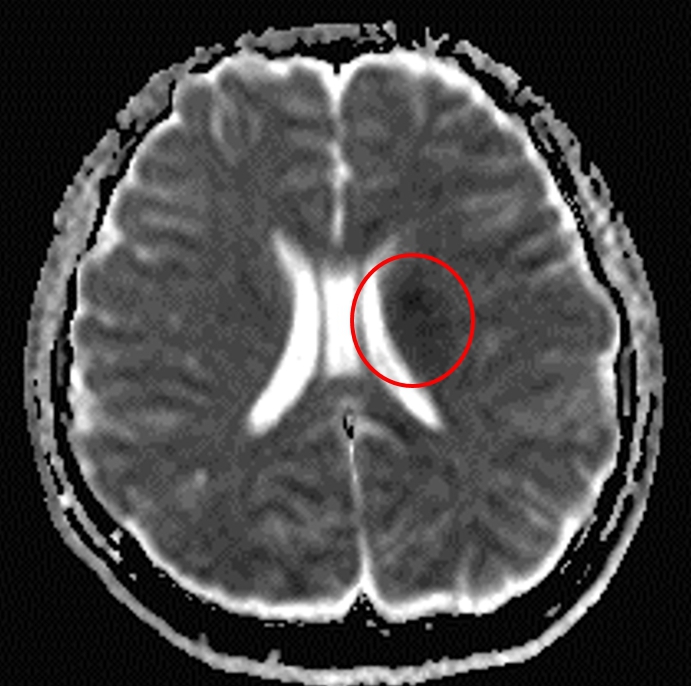

【記者張原銘、張皓傑台中報導】吳姓女大學生於校內出現突發性右側肢體無力及口齒含糊不清與構音困難,緊急送至鄰近區域醫院急診處置,經初步腦部斷層掃描後,顯示並無腦出血,而後由於症狀反覆惡化,且左側顏面神經麻痺,進一步採取腦部核磁共振造影檢查,並發現於基底核左側出現腦梗塞,因此隨即轉院至中山醫學大學附設醫院神經內科,透過一系列神經學檢查後,起初並無發現異常,胸前及經食道心臟超音波亦無看到左右心房分流,最後會診於兒童(先天性)心臟科安排微創心導管檢查,發現是「開放性卵圓孔型心房中膈缺損」所引起的腦中風,後經由「卵圓孔關閉器」順利封堵。

臨床上,腦中風分成兩大類,即出血性腦中風與缺血性腦中風,即出血性腦中風的原因是腦部的血管破裂,缺血性腦中風則是腦部的血管阻塞,而大約70%-80%的中風是屬於缺血性腦中風。

另外,腦中風的原因也包含動脈粥狀硬化所導致的血管破裂、出血或狹窄,還有心房顫動引起的血栓,以及非粥狀動脈硬化疾病,如凝血問題及動脈炎等因素,其中有25%-40%之缺血性中風找不到明確病因,被稱為「隱源性中風(cryptogenic stroke)」。

郭業文表示,「隱源性中風」在45歲以下的族群發生率較高,對患者和家庭容易造成巨大衝擊與負擔,隱源性中風可能原因很多,其中有50%隱源性中風的患者同時還有開放性卵圓孔(patent foramen ovale,PFO),容易罹患突發性臉部、單側肢體、四肢發麻無力、口齒不清或暈眩等症狀的小中風,通常會在24小時內恢復正常。

有25%的成年人卵圓孔不會自行關閉,若有來自下肢靜脈的血栓流回到心臟,有機會容易從右心房經卵圓孔到左心房,再掉到左心室後進入主動脈,最後阻塞腦部血管造成心源性腦中風的來源,而且根據研究顯示有四分一的缺血性中風患者是有機會復發,且復發會比第一次有更嚴重的肢體傷殘以及更高的死亡率。